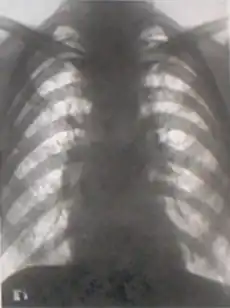

Важнейшим методом выявления силикоза была и остаётся флюорография лёгких. Однако факты свидетельствуют о том, что и не очень совершенная флюорография лёгких в 1960-х[13], и более современная в 2000-х[14], не всегда способна выявить заболевание на начальных стадиях (когда существуют наилучшие условия для сохранения жизни, здоровья и трудоспособности человека). Вскрытие 29 шахтёров, погибших во время аварии[14], и сравнение их органов дыхания с органами дыхания случайно погибших людей (не подвергавшихся воздействию пыли в шахте) показало, что при успешном прохождении медобследования (включая флюорографию) у сотрудника могли иметься изменения в лёгких, однозначно свидетельствующие о пневмокониозе. Авторы предложили дополнительные методы диагностики начальных стадий заболевания. Аналогично, вскрытие 10 случайно погибших шахтёров молибденового рудника, подвергавшихся воздействию пыли с содержанием кварца 88% в течение 3-5 лет, показало:

- Рентгенография лёгких — 1 раз в год.